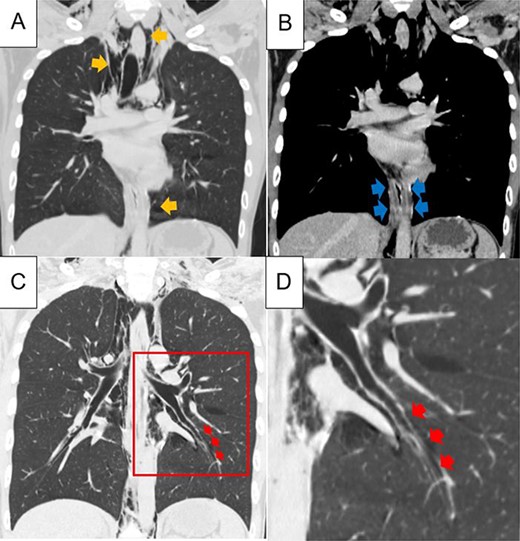

A 21-year-old man with chest pain and nausea was referred to our hospital. He had a history of admission to a psychiatric hospital with severe psychogenic vomiting. This time, he had multiple episodes of vomiting the previous day and also developed chest pain and fever of up to 38.2°C. Subcutaneous emphysema was present in the neck. Blood tests revealed a white blood cell count of 16 200 /μl. Chest CT showed extensive pneumomediastinum from the pharynges to the retroperitoneal space (Fig. 1A). The lower oesophagus was swollen and thickened, but no large wall defects, perforations or fluid collection were observed (Fig. 1B). An oesophagram was attempted to rule out oesophageal perforation, but this was not possible due to severe nausea and vomiting. Careful examination of the CT scan revealed accumulation of free air along the peripheral bronchi or pulmonary vascular sheath in the left lower lobe, which was continuous with the mediastinum (Fig. 1C, D). Based on the findings of this Macklin effect, we diagnosed that the pneumomediastinum had a high likelihood of being an SPM from the periphery of the lung rather than from oesophageal perforation. After admission, antibiotics, antipyretics and antiemetics were administered intravenously. On Day 6 after admission, the vomiting symptoms had improved, and he started eating and was discharged on Day 11. Chest CT performed on Day 15 confirmed a marked reduction of the emphysema from the neck to the mediastinum. One year later, the patient was asymptomatic and had no recurrence of SPM.

Chest computed tomography showing extensive pneumomediastinum (A; yellow arrows); the lower oesophagus is swollen and thickened, but no large wall defects or perforations and fluid collection are observed (B, blue arrows); in the left lower lobe of the lung, accumulation of free air, a finding of the Macklin effect, is found along the peripheral bronchi or pulmonary vascular sheath, which is continuous with the mediastinum (C, D; red arrows); figure D shows a magnified view of the red squares in Figure C.